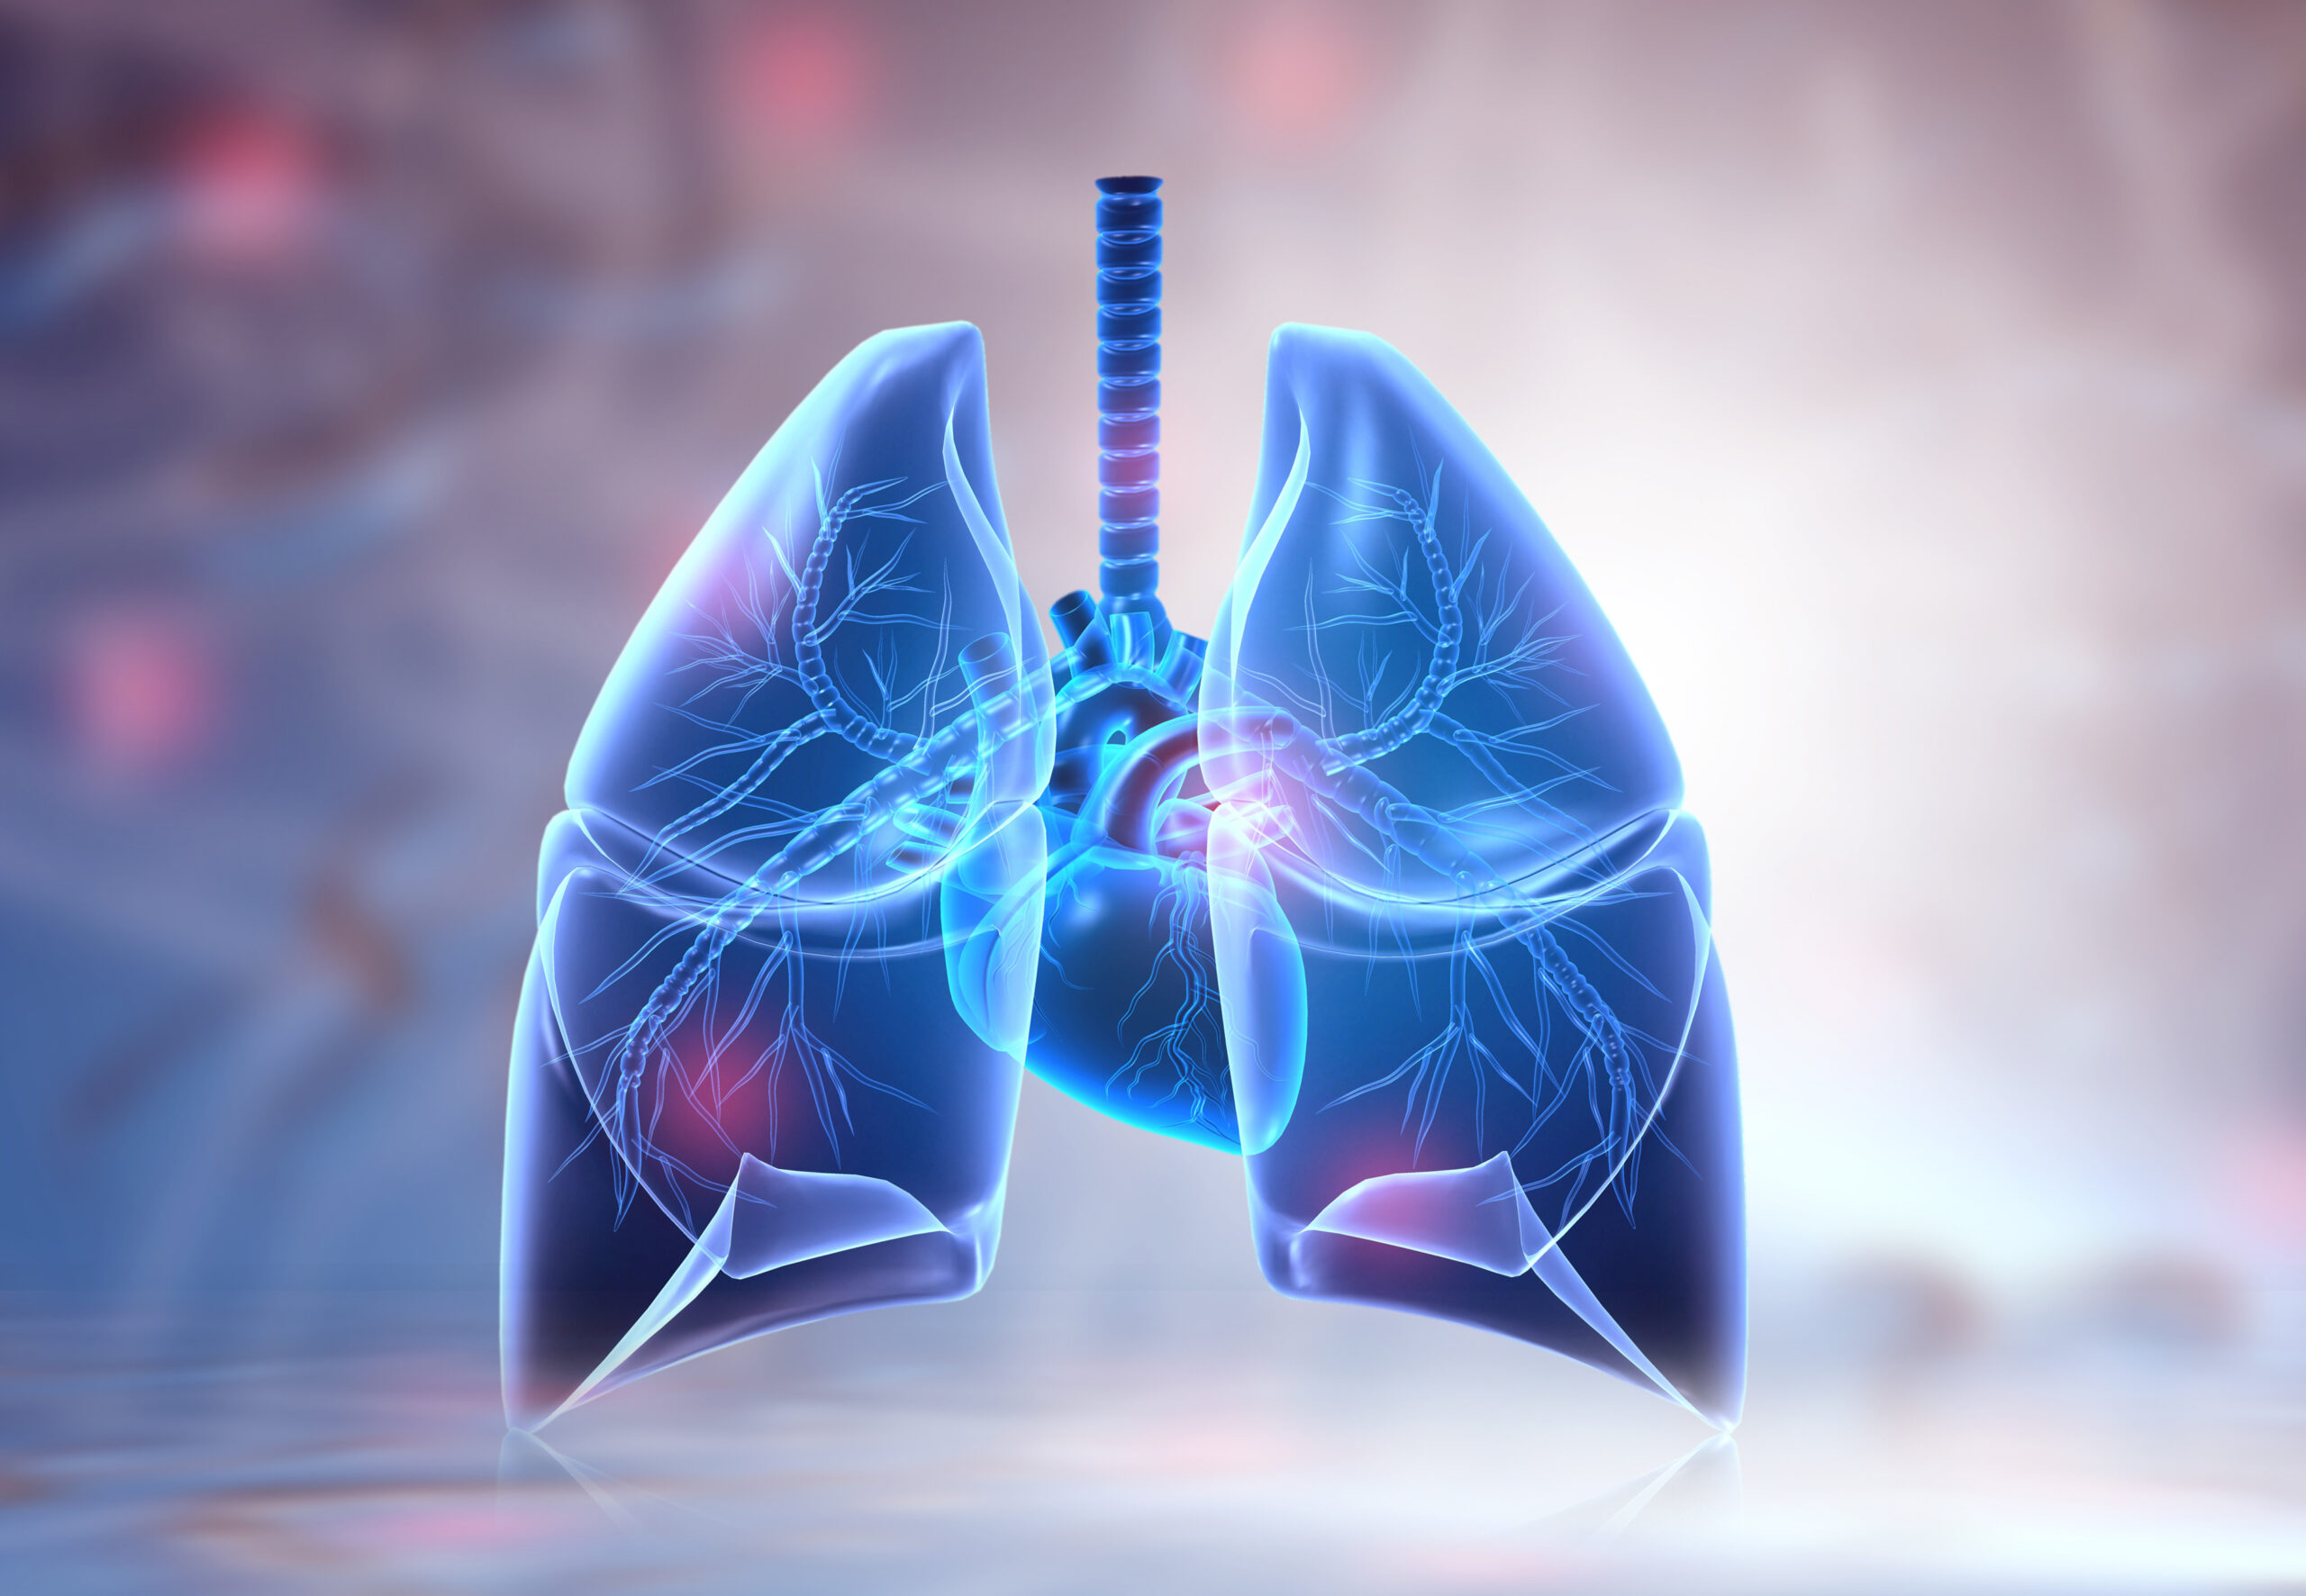

Таинство дыхания: глубокий взгляд на легкие человека в картинках

Раздел: Снимки-откровения